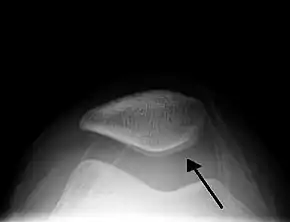

Skyline view of the patella demonstrating a large joint effusion as marked by the arrow

PurposeDetecting a knee effusion